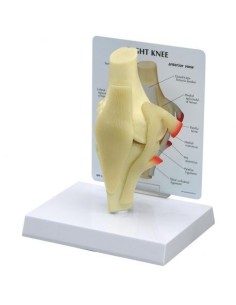

Ginocchio,W47007 modello di lusso